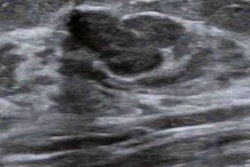

Tissue sampling is recommended for BI-RADS 4 breast lesions, as making an accurate determination of malignancy is important for preventing false-positive biopsies. Previous research suggests that CEUS has advantages in diagnostic performance over conventional ultrasound by assessing blood perfusion in breast lesions.

Wang and colleagues created a deep-learning method that incorporates multiple breast regions based on CEUS and grayscale ultrasound. They sought to determine whether using the method could lead to a reduction in false-positive biopsies and to compare its diagnostic performance with that of human ultrasound experts.